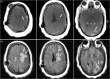

The use of flow diverting stents for wide based, intracranial aneurysms has become an invaluable treatment option. While intracranial hemorrhage and ischemic stroke from dislodged atherosclerotic emboli are common adverse events, the potential for delayed granulomatous inflammation from possible hydrophilic polymer emboli is rarely recognized. We present a unique case in which visible chipping of the pusher wire for stent placement was observed, followed by clinical and radiographic evidence suggestive of a delayed foreign body reaction to intracranial hydrophilic polymer emboli. A 55-year-old woman underwent placement of a Pipeline embolization device for a left-sided, broad-based aneurysm at the base of the internal carotid artery and posterior communicating artery. Two months later she developed right-sided focal neurological deficits. Imaging showed ipsilateral focal edema and enhancing lesions with contrast. Although not confirmed with biopsy and histopathology, clinical and radiographic evidence suggests that this patient probably experienced a delayed foreign body reaction to hydrophilic polymer emboli from compromised procedural equipment during flow diverting stent placement. Although previously described, this is the first instance to our knowledge in whichvisible chipping of the pusher wire was observed on a Pipeline embolization device.